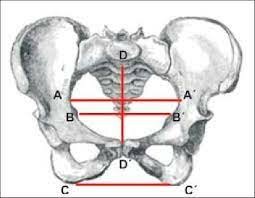

• Diámetro Pelviano

Diámetro Pelviano

Se describe diametro pelviano